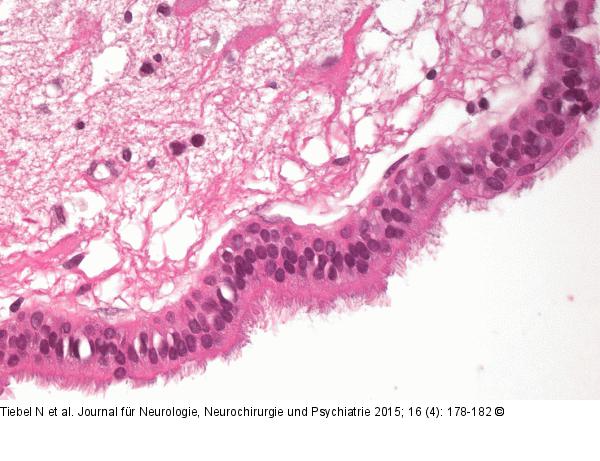

Abbildung 3: Endodermale Zyste Histologischer Befund in der Hämatoxylin-Eosin-Färbung: Die Zystenwand besteht aus mehrreihigem, hochprismatischem Flimmerepithel. Angrenzend erkennt man ZNS-Gewebe mit Ödem und reaktiver astrozytärer Gliose. |

Histologischer Befund in der Hämatoxylin-Eosin-Färbung: Die Zystenwand besteht aus mehrreihigem, hochprismatischem Flimmerepithel. Angrenzend erkennt man ZNS-Gewebe mit Ödem und reaktiver astrozytärer Gliose. |